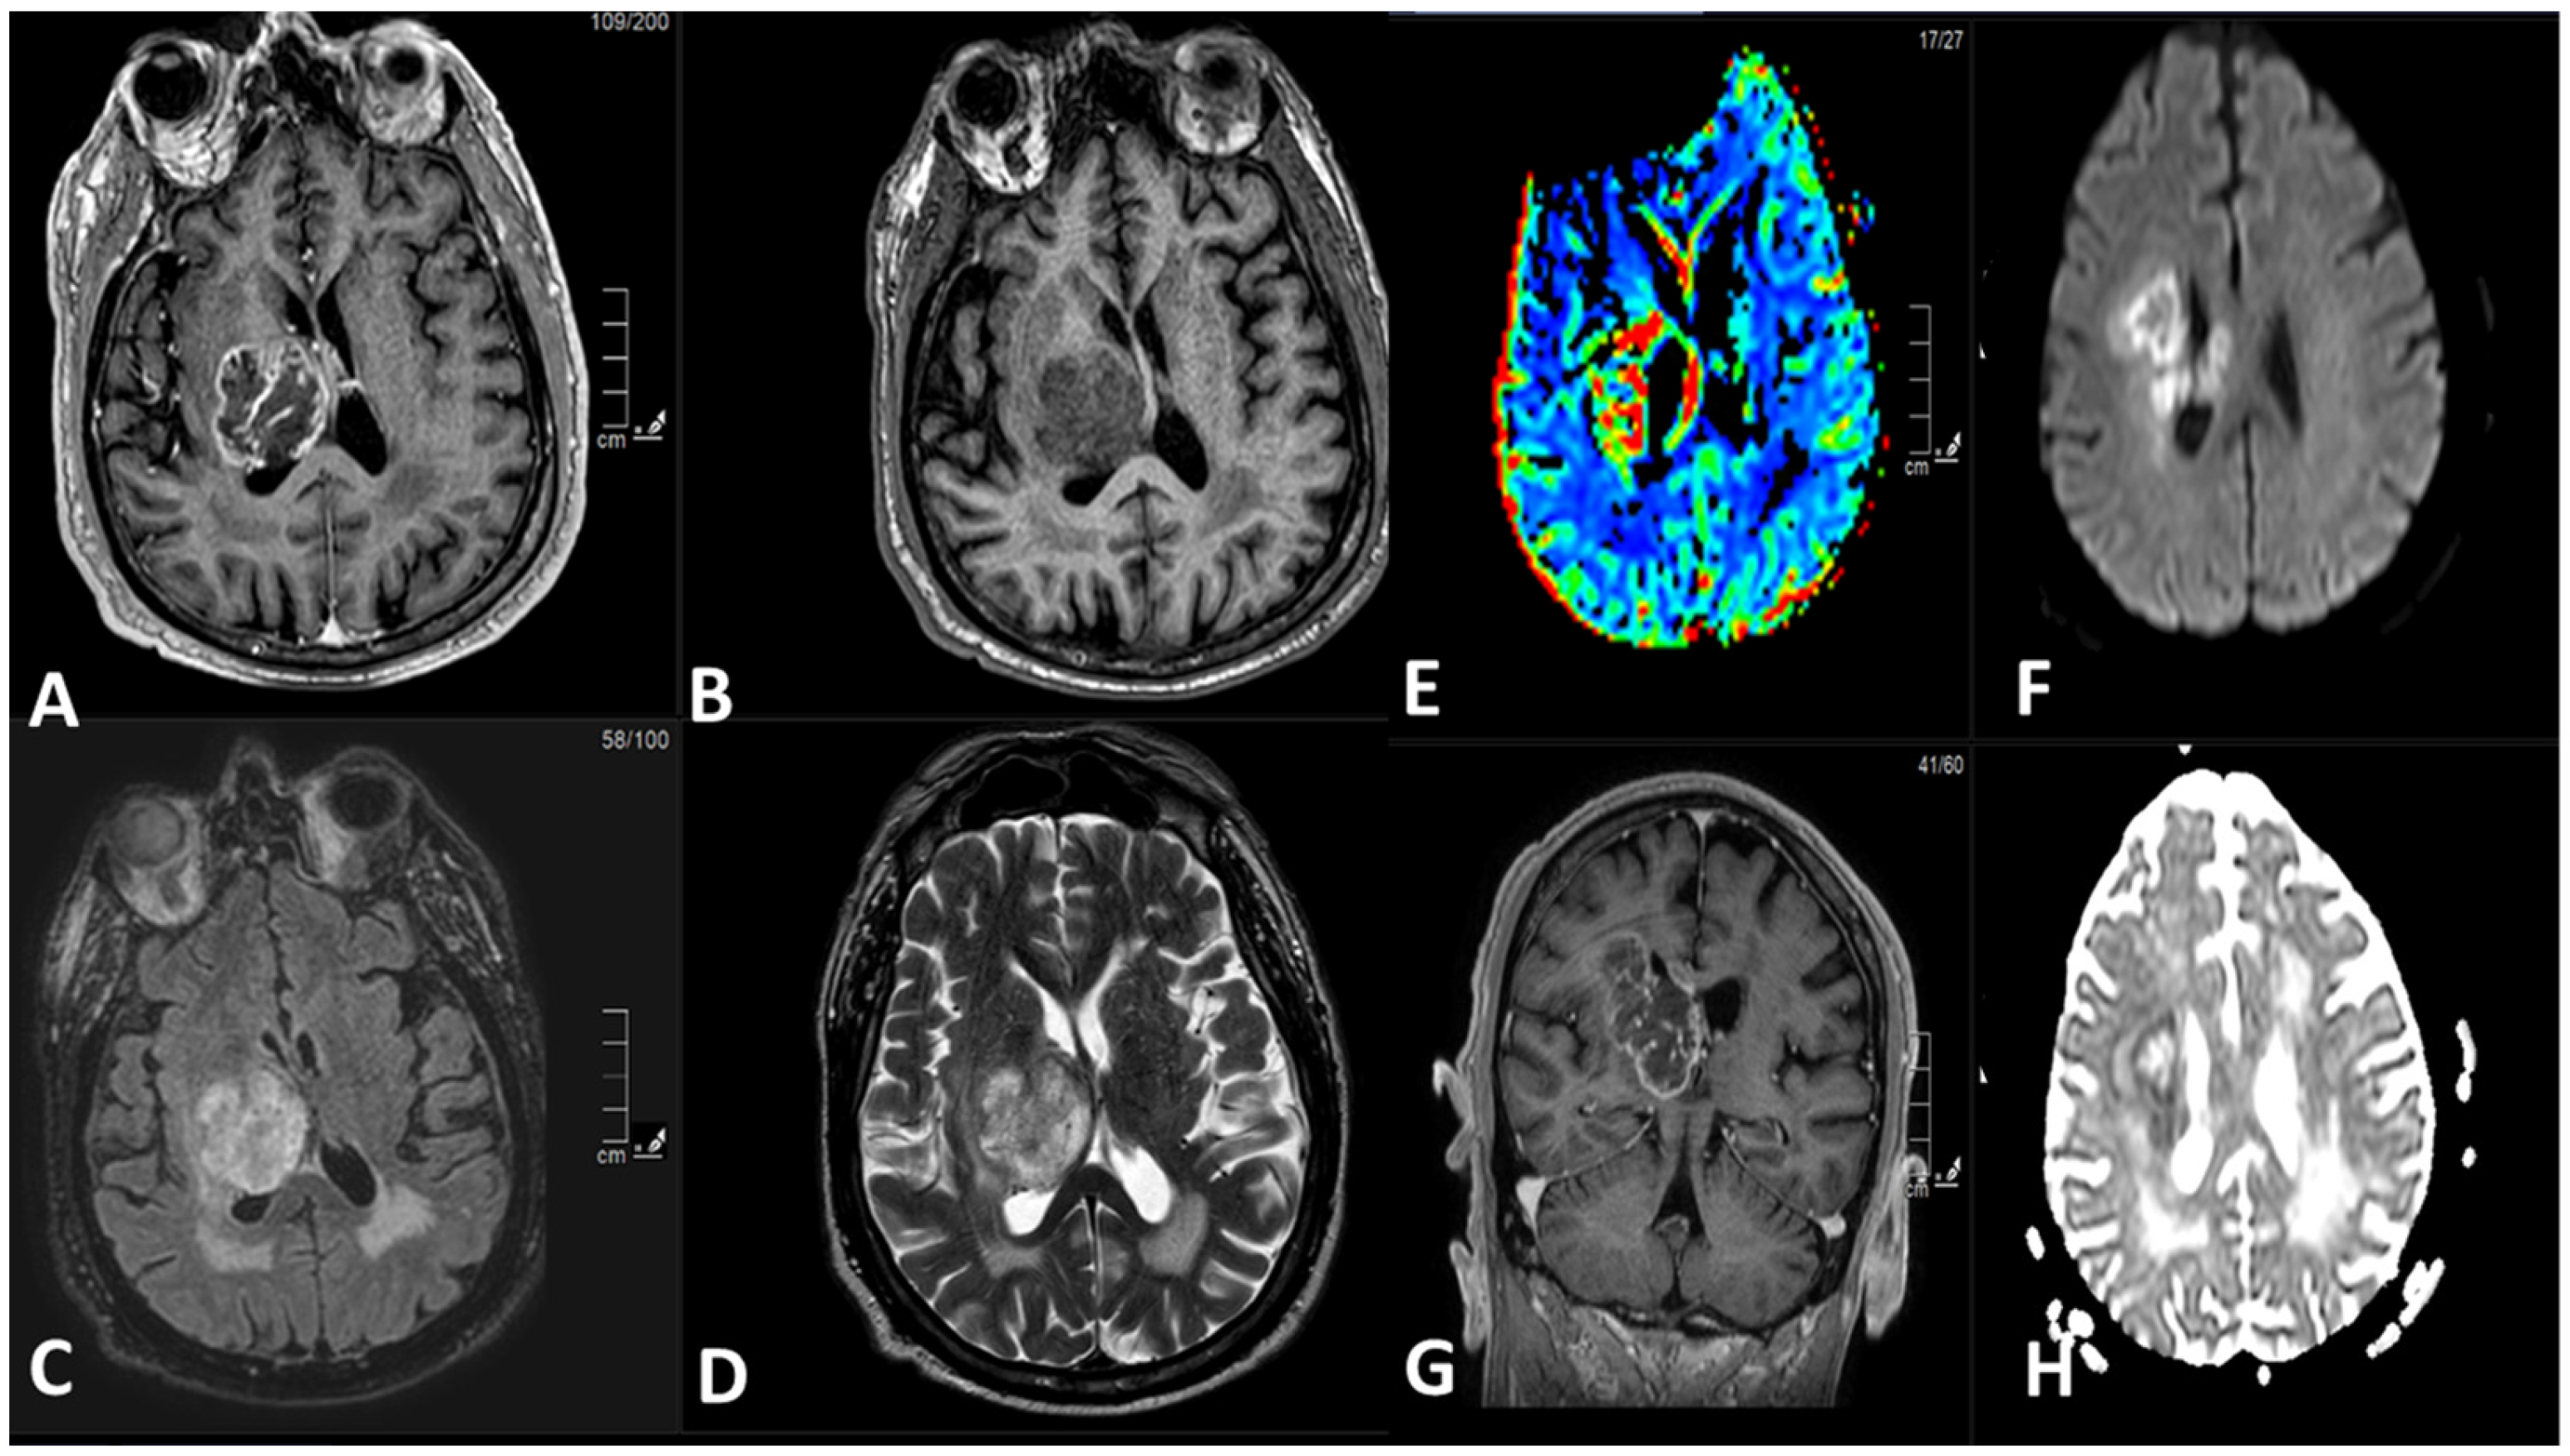

5.1. Magnetic Resonance Imaging (MRI):